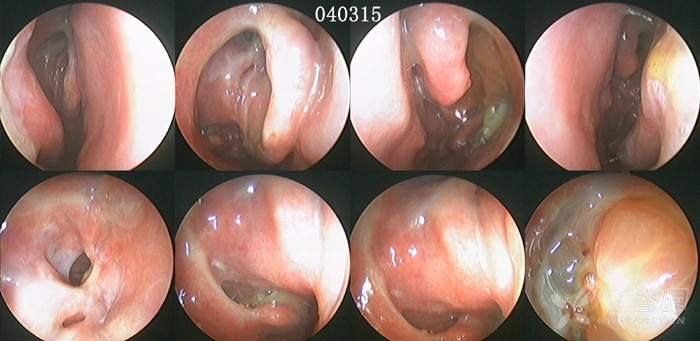

病例2:2004年2月12日手术,从手术创面的广泛性,到术后随访的频繁性,同样非常严重,站在今天鼻-鼻窦剔骨法成形术的角度,对于这样的做法和结果,既无法理解,更难以接受(见下图及图中的时间标示)。

首先,术后3-7天开始清理,之后每1-2周复诊一次,给予鼻内镜检查、清理,以及术后囊泡样变、炎症迁延、术腔粘连、窦口狭窄,对于绝大多数的患者而言,几乎就是一种常态。但频繁的内镜随访给患者带来的心理、经济、时间等各种压力,也使能够长期坚持随访者占比极少。因此,术后随访治疗能够坚持到完成粘膜上皮化的占比率,也受到了极大影响。